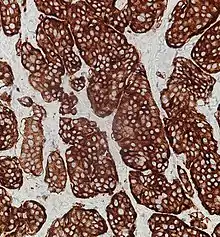

| Micrograph of a neuroendocrine tumor. H&E stain | |

NETs are often small, yellow or tan masses, often located in the submucosa or more deeply intramurally, and they can be very firm due to an accompanying intense desmoplastic reaction. The overlying mucosa may be either intact or ulcerated. Some GEP-NETs invade deeply to involve the mesentery.[72] Histologically, NETs are an example of "small blue cell tumors," showing uniform cells which have a round to oval stippled nucleus and scant, pink granular cytoplasm. The cells may align variously in islands, glands or sheets. High power examination shows bland cytopathology. Electron microscopy can identify secretory granules. There is usually minimal pleomorphism but less commonly there can be anaplasia, mitotic activity, and necrosis.